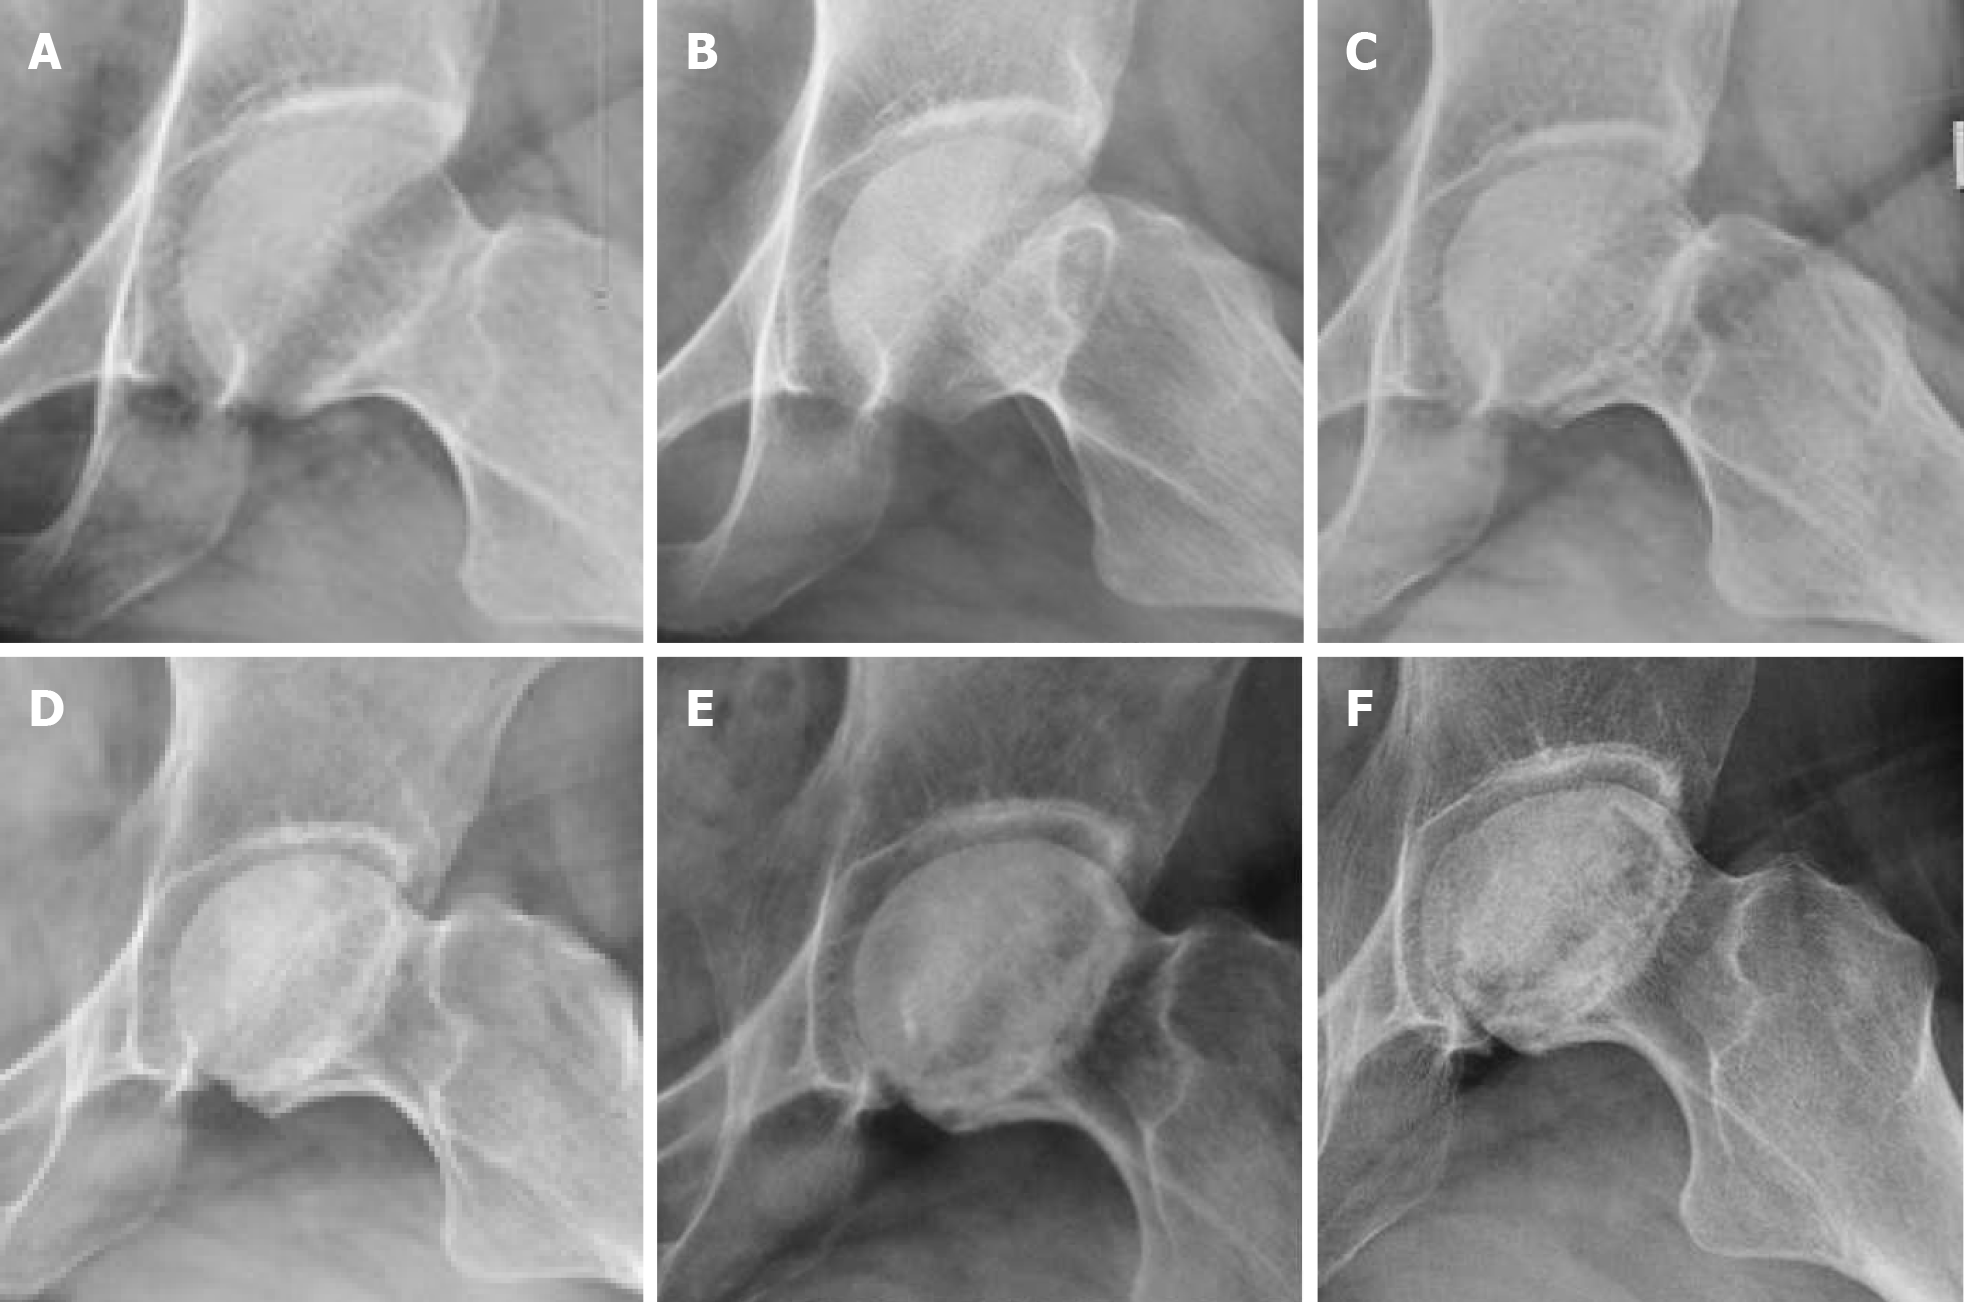

Figure 3

Figure 3 Left hip joint frog-position X-ray. A: Left hip pain for 3 months (initial visit); B: At 16 months; C: At 3.5 years; D: At 5 years; E: At 6.5 years; F: At 10 years.